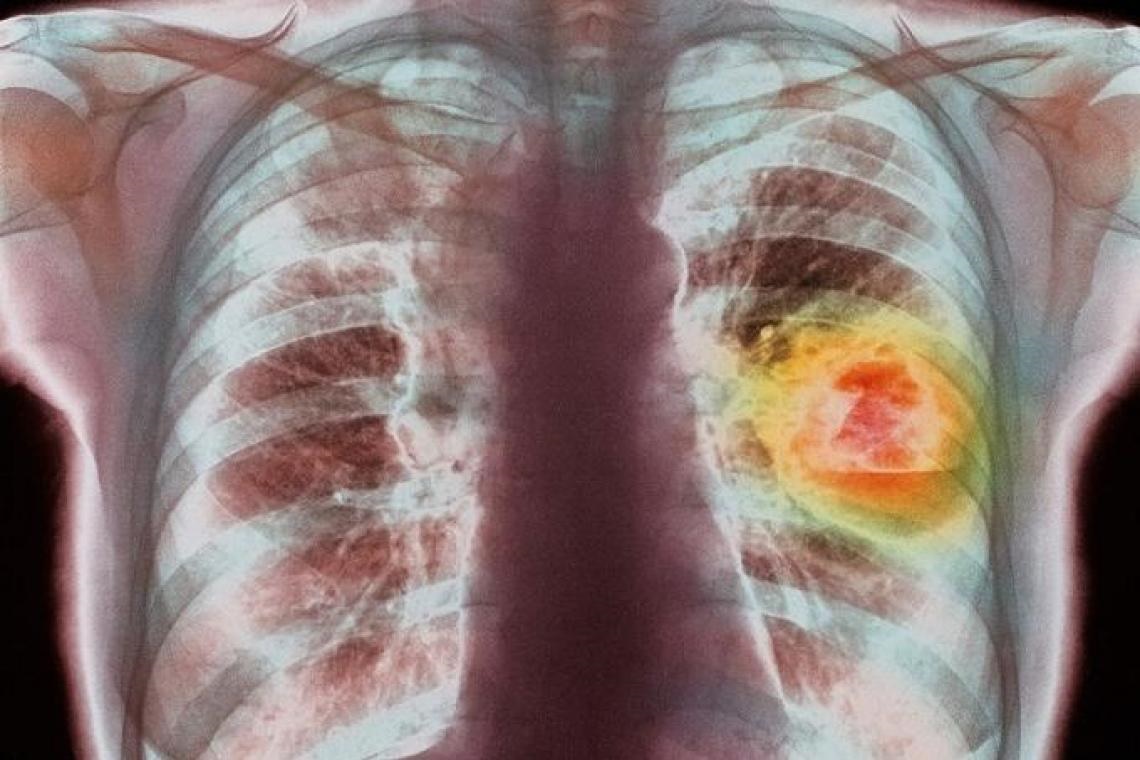

ในปี 2565 มีผู้ป่วยเป็นจำนวนมากที่ตรวจพบว่าเป็นโรคมะเร็งปอดในประเทศไทย ซึ่งยังคงเป็นสาเหตุของการเสียชีวิตเป็นอันดับ 2 ของคนไทย (ในผู้ชายรองจากมะเร็งตับ และเป็นอันดับ 1 ในผู้หญิง) ซึ่งการตรวจคัดกรองให้พบโรคมะเร็งปอดในระยะแรกนั้นทำได้ยาก จึงทำให้มีอัตราการเสียชีวิตสูง โดยผู้ป่วยเหล่านี้มากกว่าครึ่งที่ตรวจพบมักจะเจอในระยะลุกลาม เนื่องจากอาการของโรคนี้มักไม่มีอาการ ส่งผลทำให้ผู้ป่วยได้รับการวินิจฉัยล่าช้า อย่างไรก็ตาม ก็ยังมีผู้ป่วยจำนวนมากที่สามารถรักษาแต่กลัวการผ่าตัด เนื่องจากยุคเริ่มต้นของการผ่าตัดปอดนั้น ได้ริเริ่มทำโดยการเปิดช่องอก ซึ่งมีความจำเป็นในการที่ต้องตัดกล้ามเนื้อหลายมัดและถ่างขยายกระดูกซี่โครงในการเข้าไปทำการผ่าตัด จึงทำให้ผู้ป่วยค่อนข้างกังวลและเกิดอาการกลัวในการรักษาโรคมะเร็งปอด อย่างไรก็ตาม ปัจจุบันการผ่าตัดปอดได้มีการพัฒนาโดยเฉพาะการผ่าตัดส่องกล้อง ส่งผลทำให้การผ่าตัดปอดนั้นเป็นการผ่าตัดที่ปลอดภัย โดยในผู้ที่ไม่มีโรคประจำตัวโอกาสที่จะมีความเสี่ยงต่อการเกิดภาวะแทรกซ้อนที่รุนแรงนั้นมีน้อยกว่า 1 เปอร์เซ็นต์